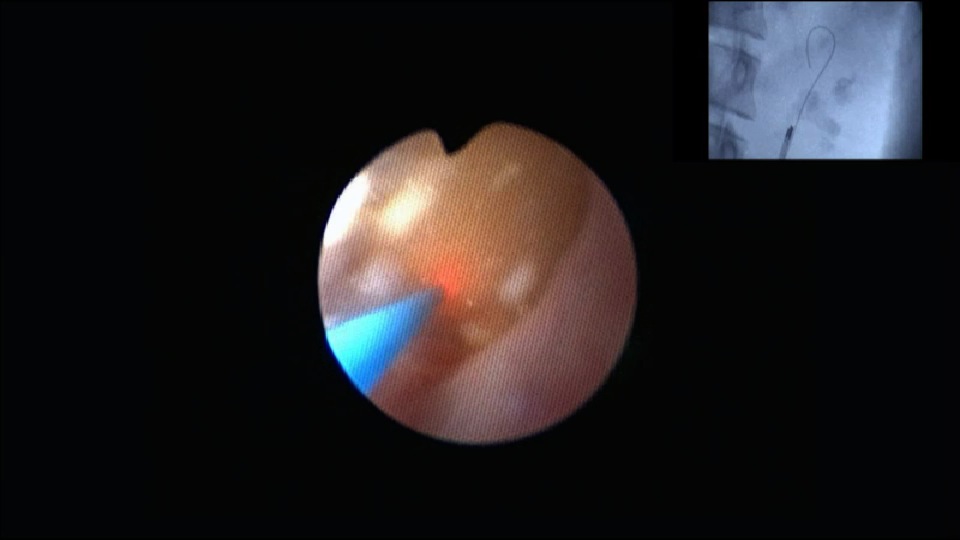

Urétérorénoscopie souple chez l'enfant